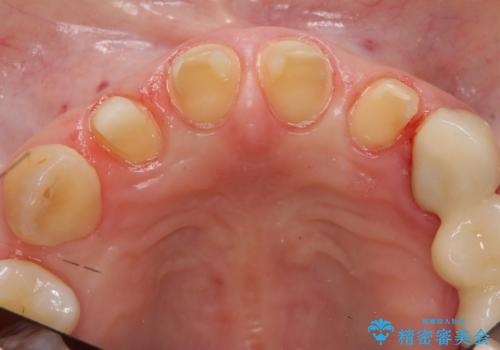

前歯の虫歯 つぎはぎの歯をセラミックに

- 矯正治療後に、前歯の樹脂の詰め物のやりかえを提案していましたが、治療は当時行いませんでした。

その後3年間来院がなく、その間に前歯の虫歯の進行があり、治療を行いました。

やはり、樹脂で虫食い状になってしまうと虫歯が進行しやすくなっているためクラウンがおすすめです。

下の前歯との距離(クリアランス)が大きくは取れなかったため、ジルコニアクラウンではなくe-maxクラウンにしました。